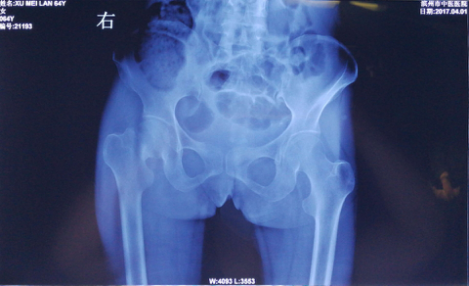

患者许某,女,64岁,因骑电车不慎翻车导致右髋部疼痛肿胀,活动受限。来我院进行就诊,医生对其进行了各项化验检查,确定为右股骨颈骨折入院。入院后,为了保障患者早日恢复肢体功能,我院骨伤科专家开会研究,决定对患者施行右侧人工股骨头置换手术。

术前X线片